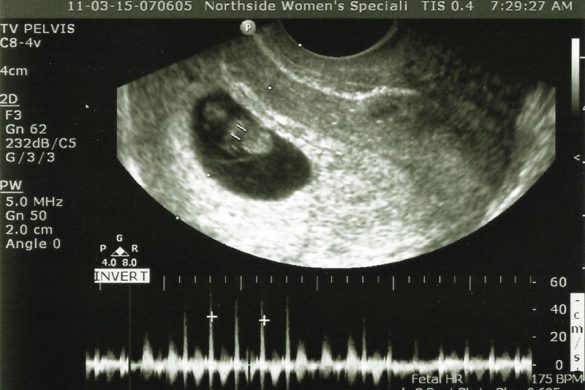

I think you could hear a pin drop as everyone in the room was waiting to see the results. As they started the ultrasound…I saw it. Our baby…alive…growing and with a heart that was strong and beating quickly. They took the measurements and we were at 8 weeks on the dot. Next…they hit the switch and I heard it for the first time.

Our babies heart was beating at a strong 175 bpm.